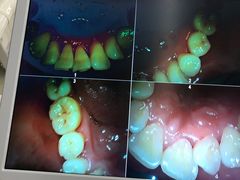

• -牙博士口腔品牌连锁(杨浦店)

lp1943 | 21-01-30

报错